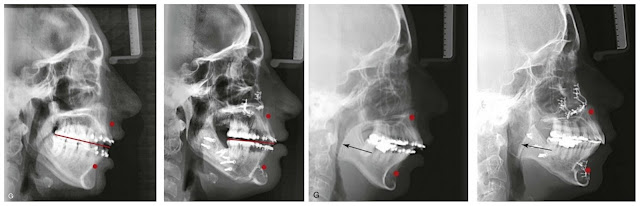

In the majority of people who have a recessed face, you will find that their nose seems to be a little bit out of place, with its large size and shape of a curved beak. It is only an ILLUSION. We do not inherit the shape of our noses. That is completely dependent on how much support the hard tissues of the maxilla and nasal bone provide to the soft tissues of the nose, including cartilage. At the base of the opening to the nasal cavity, is located one small bony projection called ANTERIOR NASAL SPINE (ANS). I added an x-ray scan of a person who has a good-looking face. Notice the ANS. It is in a relatively horizontal position, just like the occlusal plane, right?

Now take a look at the anterior nasal spine in my scans (marked red for better visualization). It is not horizontal at all; instead, it is slanted, just like my occlusal plane. Do not confuse ANS with cartilage (ANS is sharp and pointy, not dull)!

The anterior nasal spine serves as a support for the cartilage of the nasal septum, and so it is responsible for the shape of our noses. When the upper jaw is recessed, the ANS, as a part of the maxilla, is recessed as well. People with adenoid faces often have an aquiline nose (shaped like the beak of an eagle). That is no coincidence, but rather the sagging of the nasal soft tissues due to not having anatomical support. Sayings such as French nose, Roman nose, or Jewish nose are in fact based on a mere illusion where the person’s nose is not massive/hooked but rather his/her jaws are down-swung (hence the upper jaw doesn't support the soft nasal tissues - only the nasal bone does).